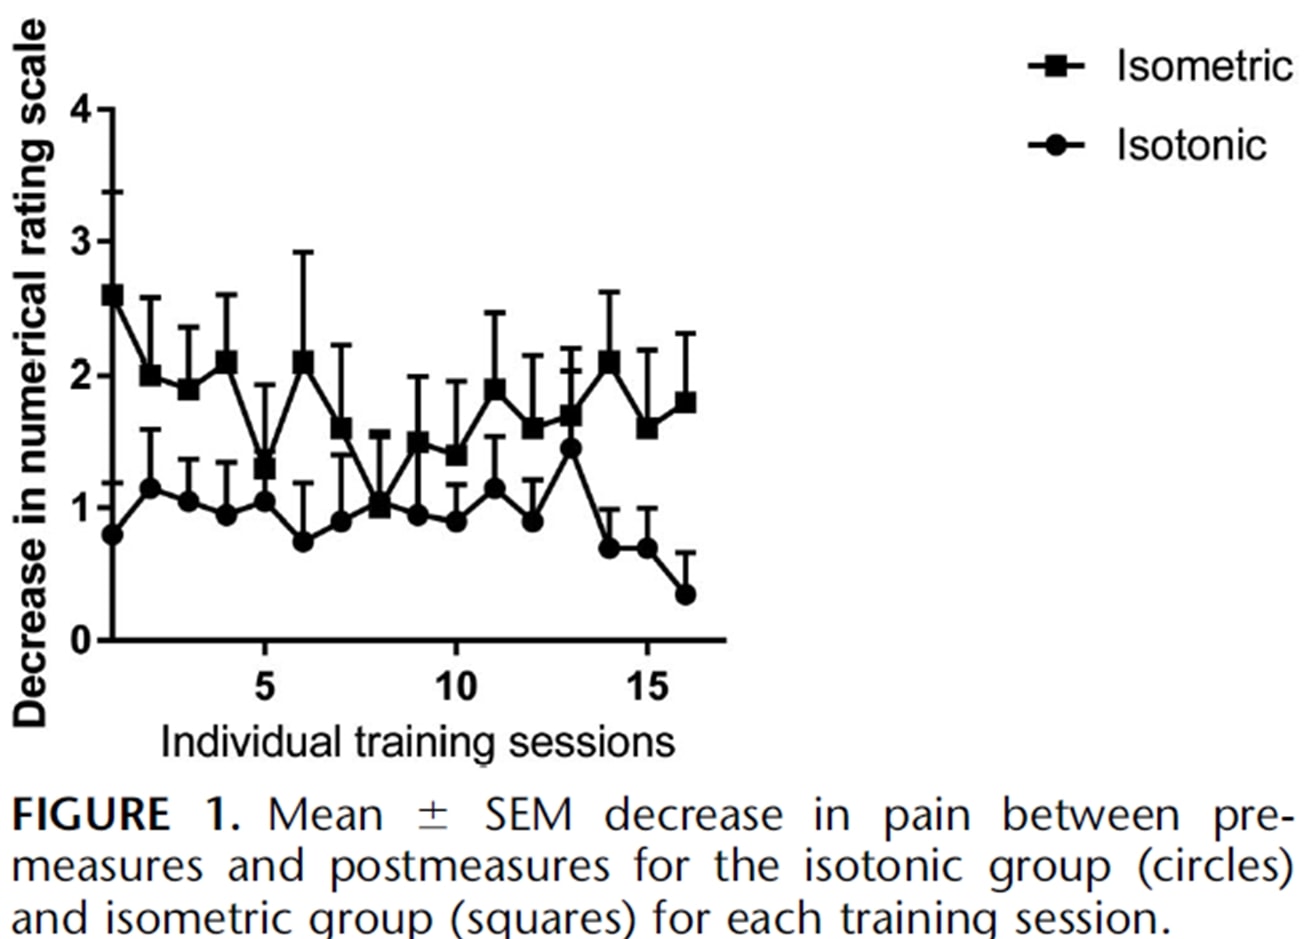

Los mismos autores realizaron un estudio de seguimiento en temporada con atletas de salto dos años después (Rio et al. 2017) en el que compararon un programa isométrico y otro isotónico entre sí. En este estudio, los resultados fueron un poco más heterogéneos en ambos grupos, con una mayor disminución inmediata del dolor en el grupo isométrico:

Un estudio reciente de Holden et al. (2019) analizaron el efecto de los isométricos también en la tendinopatía rotuliana y no encontraron ningún efecto analgésico:

Figura de Holden et al. (2019)

Sin embargo, un alto porcentaje de mujeres y una edad media relativamente elevada no son típicos de la tendinopatía rotuliana, que suele ser una enfermedad de hombres jóvenes que saltan. Así que podría ser que el diagnóstico de tendinopatía rotuliana no fuera correcto en algunos casos. Ahora bien, aunque esos dos estudios se realizaron para la tendinopatía rotuliana, veamos si podemos transferir estos resultados a otros tendones.